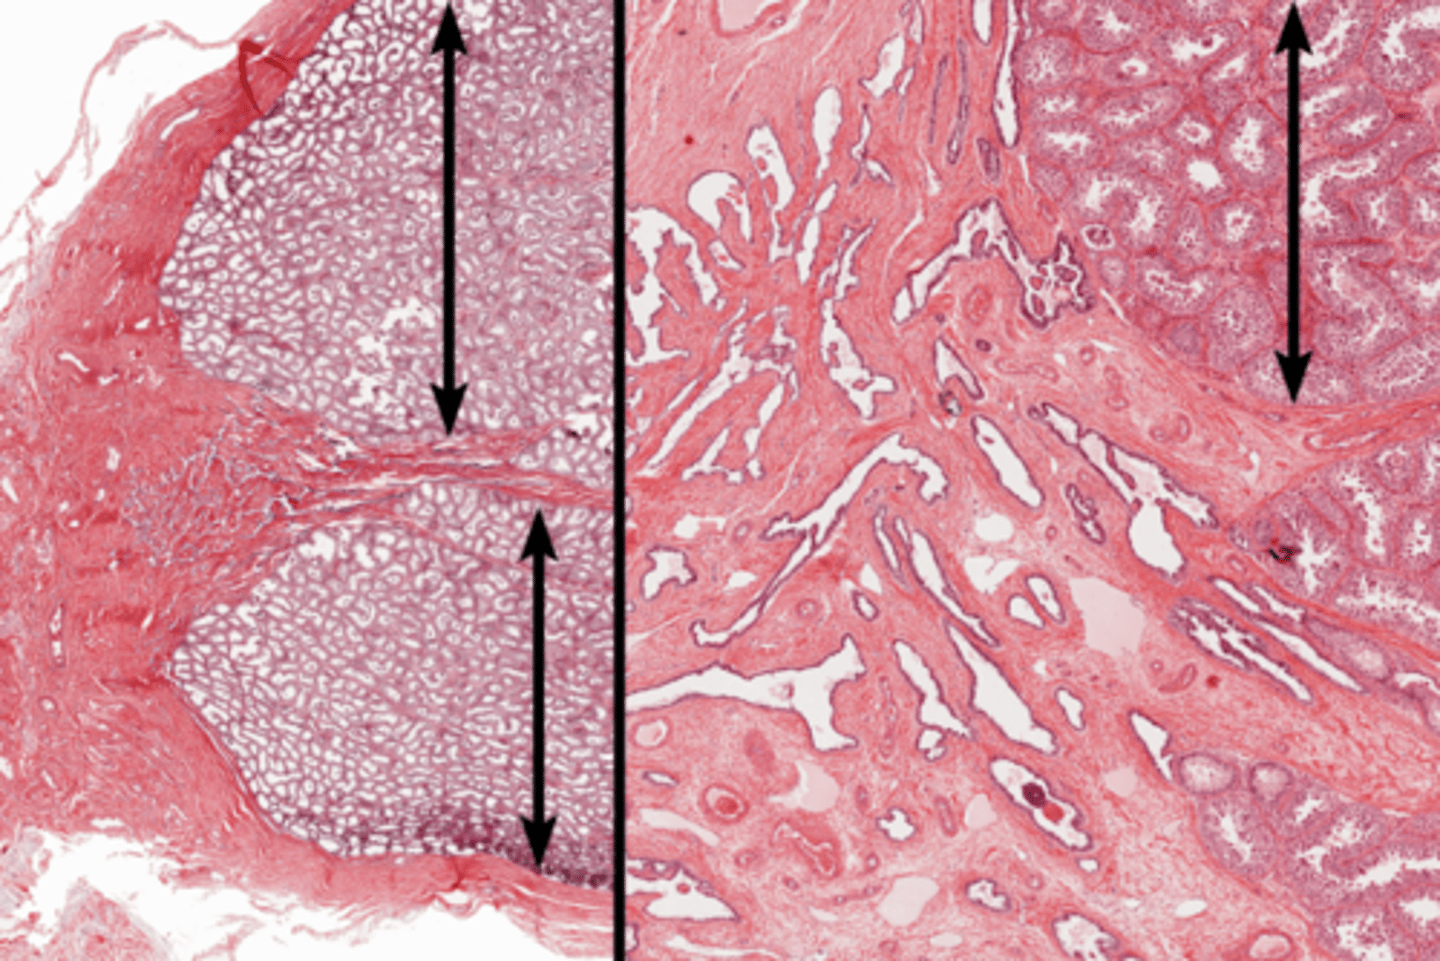

Tunica albuginea

Tunica vaginalis

Seminiferous tubules

Seminiferous tubules

Lobule

Septum